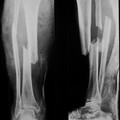

Компартмент-синдром - это как снежный человек - много разговоров, но мало кто видел. Но этот "снежный человек" однозначно существует. Я лично тоже не видел. Хотя имел полный шанс созерцать его.Но этому "шансу" не дал реализоваться. Мы придерживаемся своей тактики профилактики данного грозного осложнения: 1. Минимально травматичная, максимально точная и быстрая репозиция костных отломков, а также максимально стабильная их фиксация; 2. Интра- и послеоперационное дренирование гематомы; 3. максимальный покой конечности. В приведенном случае течение компартмент-синдрома усугубилось травматичностью оперативных вмешательств и продолжающимся кровотечением как одного из факторов повышения внутритканевого давления за счет внутри- и межфасциальных гематом. К тому же отсутствует вторая проекция рентгенограмм. Но даже на имеющейся репозиция оставляет желать лучшего. Атравматичная, точная и быстрая репозиция расчитана на закрытие костной раны и, соответственно препятствует образованию гематом. Дренирование уже имеющихся гематом также является немаловажным фактором. Спицевые отверстия в мягких тканях являются неплохими дренажами. Иногда в местах наиболее эффективного дренирования гематомы мы вводим и оставляем на несколько дней торчащие из тканей отрезки спиц. Как правило, этих мероприятий достаточно, чтобы не дать развиться этому грозному осложнению.

В подтверждение привожу снимки пациента И., 66 лет, поступившего с тяжелой сочетанной травмой через 3 суток после получения травмы. Объективно при поступлении - огромный, болезненный, напряженный отек голени, парестезии и ослабление пульсации на стопе. Прооперирован в день поступления. Все сделано так, как было описано выше. В послеоперационном периоде все признаки синдрома быстро пошли на спад. Начал приступать на конечность через 3 суток после операции, через две недели давал умеренную нагрузку, а через месяц мог ходить без дополнительных средств опоры.